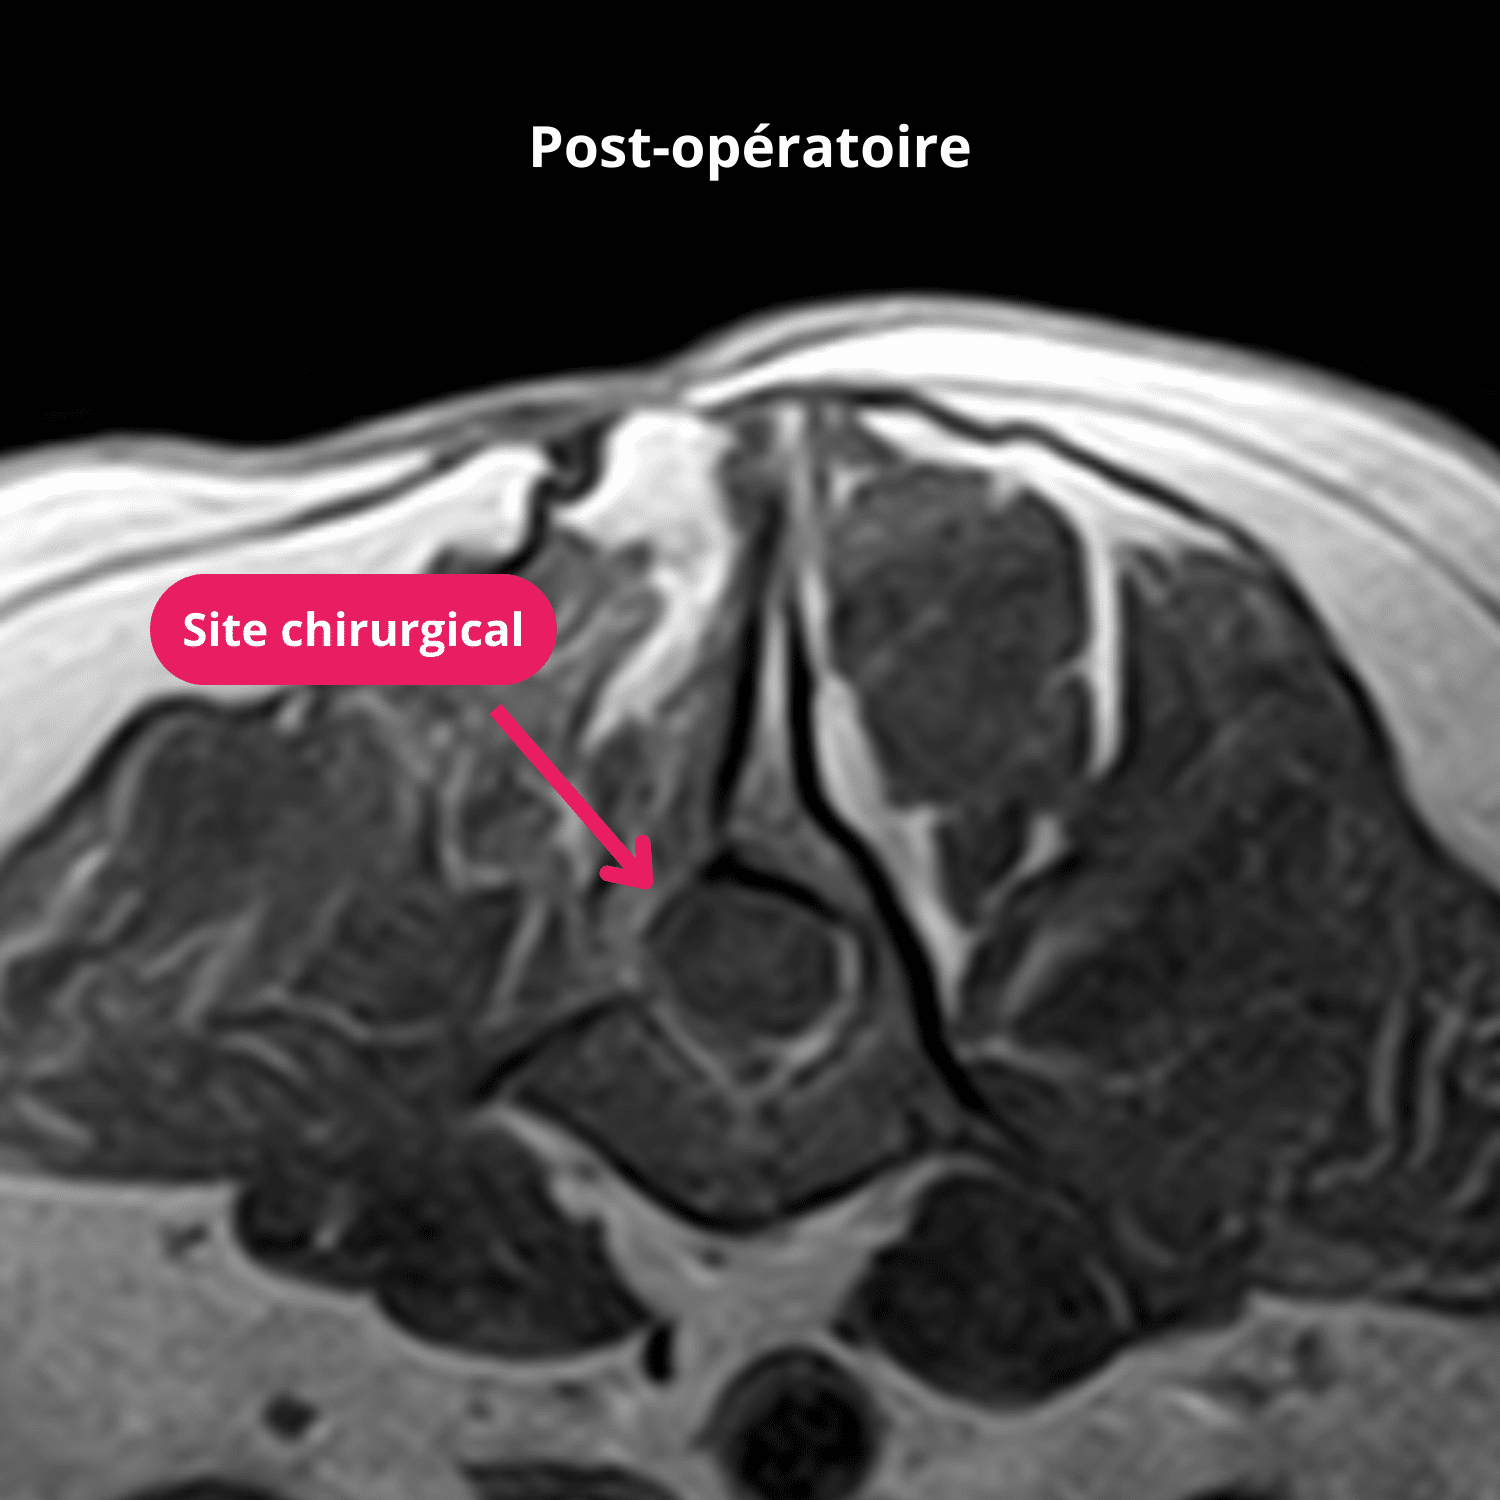

Un contrôle à 5 mois post opératoire est réalisé. Lors de celui-ci, l’examen général et nerveux de l’animal sont sans anomalies et le chien est parfaitement ambulatoire. L’IRM ne révèle aucune anomalie médullaire ou vertébrale en regard du site chirurgical excepté un tissu cicatriciel non actif.

Une nouvelle IRM de la colonne montre une compression médullaire focale, extradurale latérale droite sévère avec une portion foraminale en regard du disque T11-T12 par du matériel minéralisé. L’ancien site d’hémi-laminectomie est visible en L2-L3 à droite et ne montre aucune anomalie, ni aucune récidive tumorale.